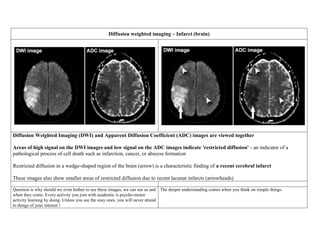

Diffusion weighted imaging – Infarct (brain)

Diffusion Weighted Imaging (DWI) and Apparent Diffusion Coefficient (ADC) images are viewed together

Areas of high signal on the DWI images and low signal on the ADC images indicate 'restricted diffusion' - an indicator of a

pathological process of cell death such as infarction, cancer, or abscess formation

Restricted diffusion in a wedge-shaped region of the brain (arrow) is a characteristic finding of a recent cerebral infarct

These images also show smaller areas of restricted diffusion due to recent lacunar infarcts (arrowheads)